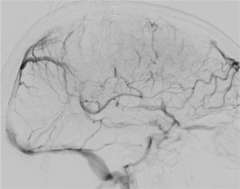

Cerebral venous sinus thrombosis is a rare condition when a large blood clot forms in a large vein in the brain called a dural venous sinus. The clot blocks the dural sinus and prevents the blood flow draining from the brain (Figure 1).

Brain imaging studies such as MRI and CT are commonly used to demonstrate the clot in the cerebral venous sinuses. If necessary, catheter angiography is also performed to visualize the relatively small clots or when catheter based clot-removing treatment is needed (Figure 1).